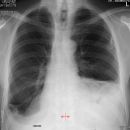

Kardiomegalie